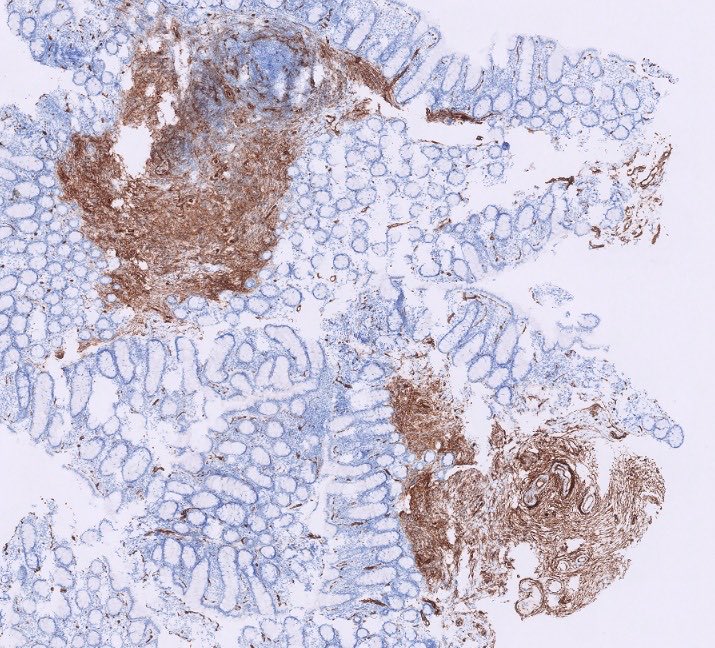

35 yo female with a thyroid neoplasm and extensive lymph node metastases. FNAC indicates Bethesda VI - PTC. What would you call it?

Annamária Ribiánszky, MD tweet mediaAnnamária Ribiánszky, MD tweet mediaAnnamária Ribiánszky, MD tweet mediaAnnamária Ribiánszky, MD tweet media